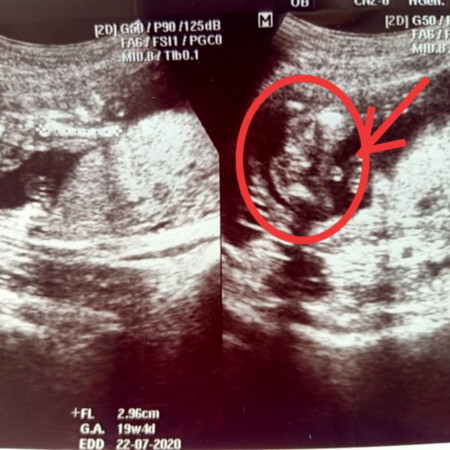

แบบนี้เพศหญิง/ชายค่ะ

รบกวนแม่ๆ ช่วยดูหน่อยค่ะ

บ้านนี้หมอบอกว่าได้ลูกชาย แม่ก็ดูไม่ออกสักที 😁😁😁

ชายค่าา บ้านนี้ก้อได้ชายเหมือนกัน 😅

ผู้ชายท่าโพสเดียวกันเรยค่ะ

ชายจร้า พวงไข่ชัดมากแม่😂😂

จากที่ดูน่าจะชายค่ะ

น่าจะผู้ชายค่ะ

น่าจะชายนะคะ

น่าจะชายค่ะ

ผู้ชายคะแม่